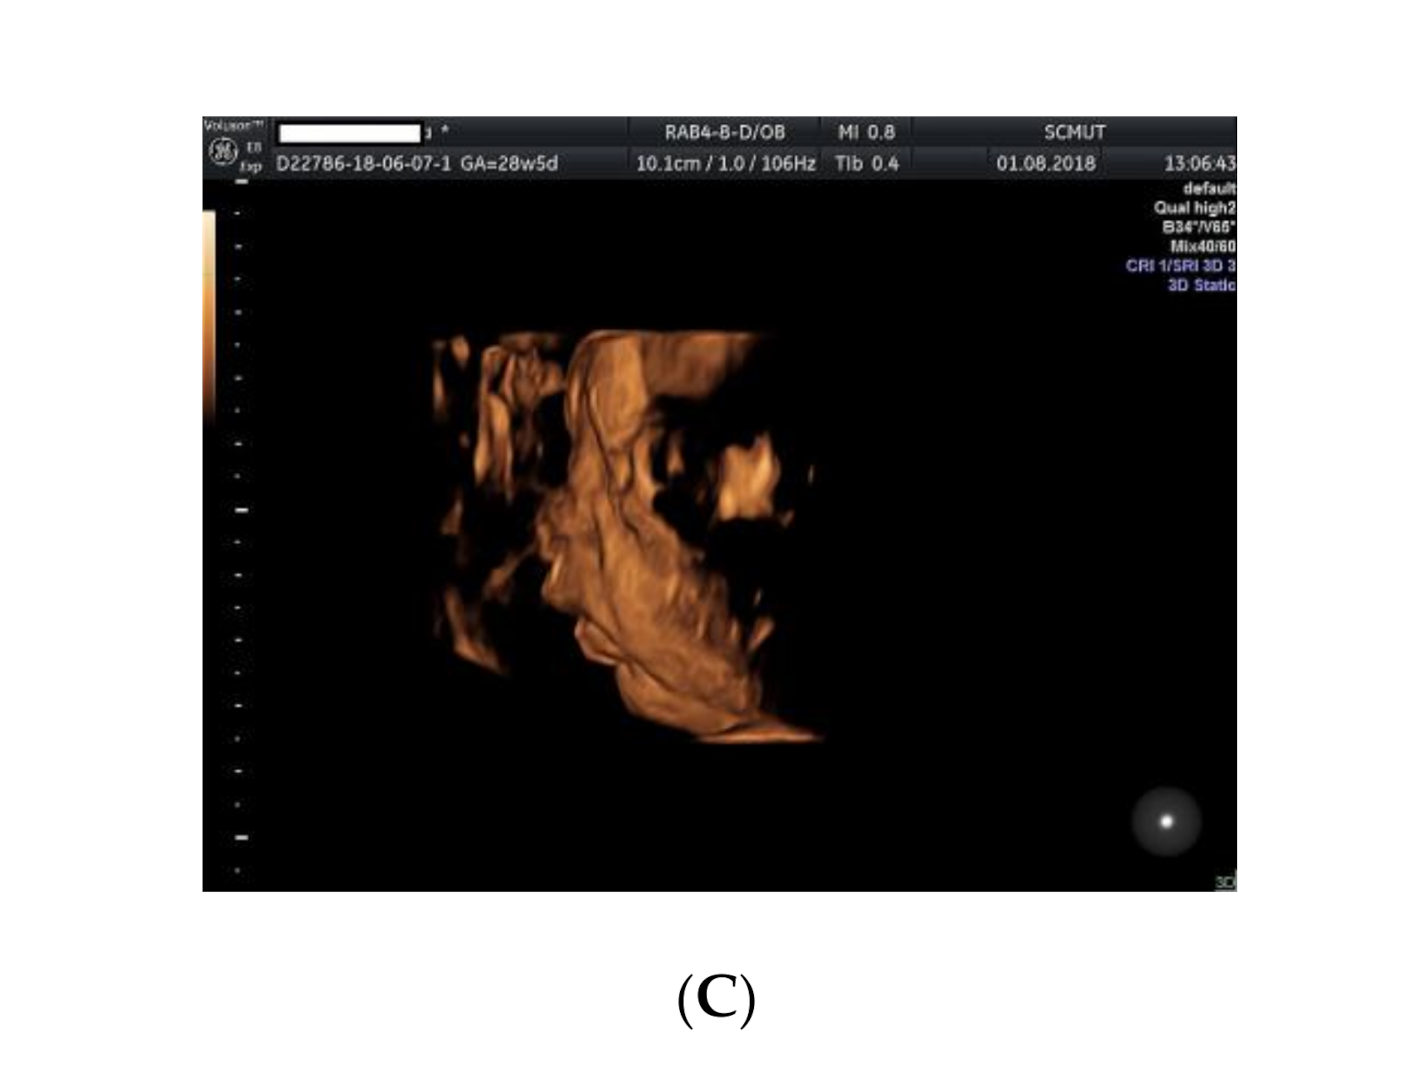

2. Case Presentation